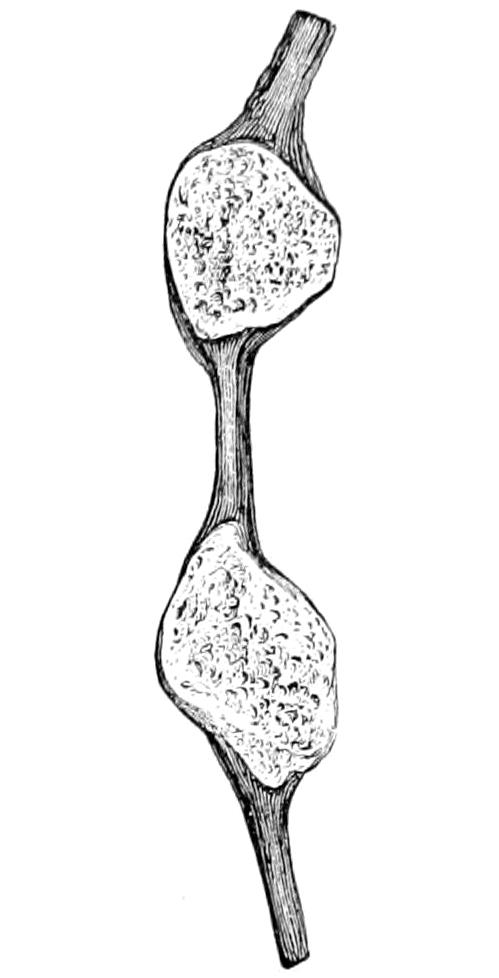

Fig. 1

Congenital hypertrophy: gigantism of both lower extremities. (Case of Dr. Graefe [Sandusky].)